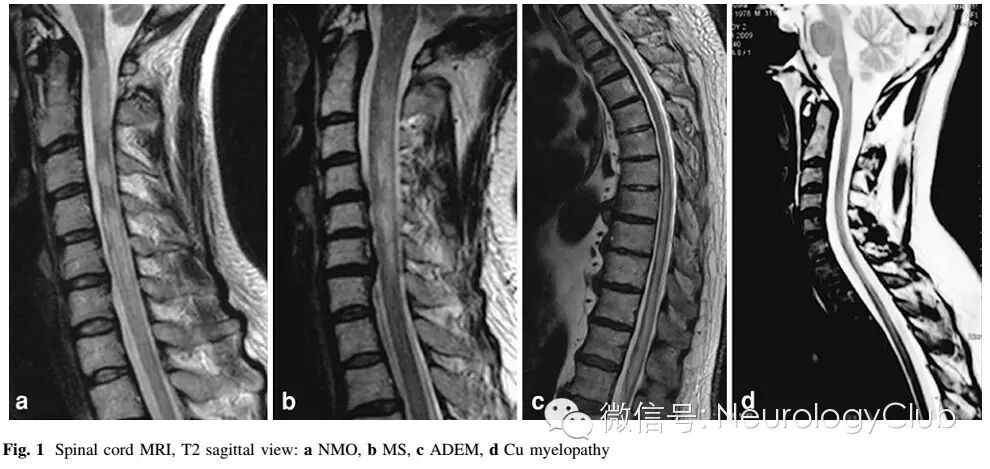

1视神经脊髓炎

(AQP4阳性的NMO患者。A-B:C2-T10可见长节段脊髓病灶,脊髓中央水肿,呈T2WI高信号,T1WI低信号;C:横断面T2WI脊髓周围白质未受累)

多发性硬化

头颅MRI

符合Barkhof标准;

Dawson手指征和近皮层的U型病灶

脊髓MRI

脊髓肿胀与强化较NMO少见;有其他病灶存在

急性播散性脑脊髓炎

病灶较大且融合成片。基底节区常受累